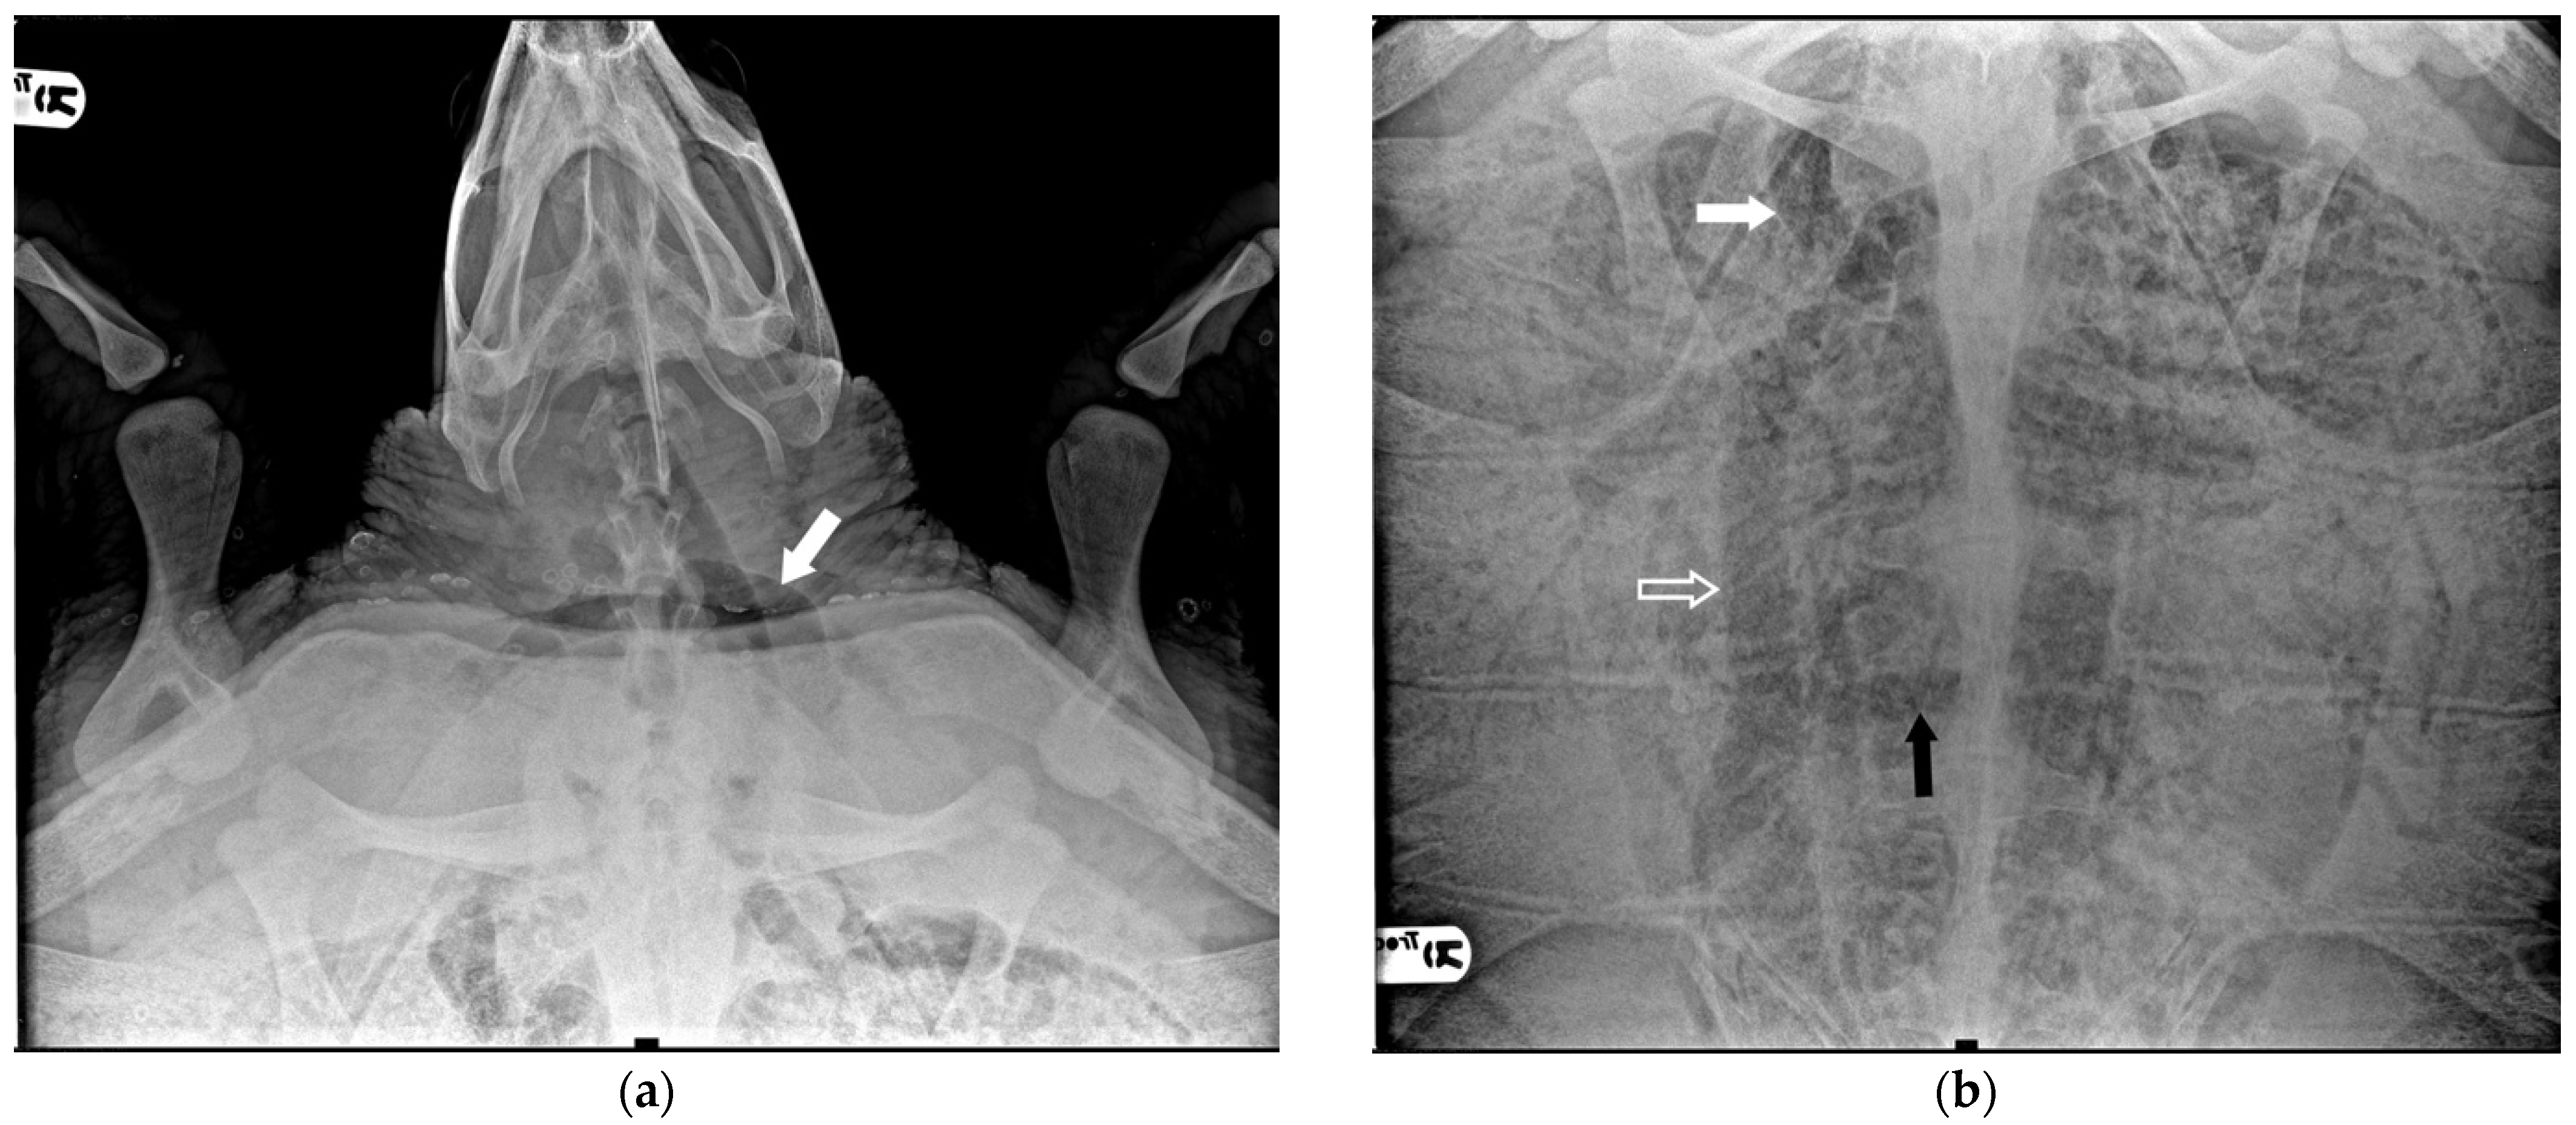

Specifically, eight animals were classified as negative (27.6%): they exhibited no radiographic signs of gas presence in any of the considered districts. In the case of 11 turtles, gas was observed in only a few anatomical areas, primarily in the marginal-costal vessels and/or renal vessels, leading to their classification as mild cases (37.9%) (Figure 1).

Four subjects were classified as having moderate severity of GE (13.8%): in addition to the renal and marginal-costal vessels, a notable distribution of gas was identified in several other vascular districts, including hepatic vessels, inferior mesenteric artery, gastric artery, abdominal transverse vein, iliac arteries, and veins (Figure 2).

Six turtles were categorized as severe (20.7%) because, apart from all the more peripheral districts, a significant presence of gas was observed in central vascular districts such as the precava vein, postcava vein, venous sinus, left atrium, pulmonary artery and vein, pulmonary trunk, aorta, and brachiocephalic trunk (Figure 3).

Figure 1. R-ray examination in DV projection of a loggerhead turtle affected by mild GE. It is possible to detect a small amount of gas within the renal vessels (indicated by white arrows).

Figure 2. X-ray examination in DV projection of a subject diagnosed with moderate severity GE reveals the presence of gas in various vessels, including the gastric vessels (white arrow), inferior mesenteric artery (white empty arrow), iliac vessels (black arrow), and duodenal vein (black empty arrow). The present gas overlaps the lungs’ cranial area, reducing the visualization of lung volume.

Figure 3. X-ray examination in DV projection of a subject diagnosed with severe GE. An evident massive presence of gas in the majority of vessels: (a) the white arrow shows the subclavian artery; (b) the white arrow shows the massive presence in the precaval vein, the white empty arrow the postcava vein, the black arrow the transverse vein, obscuring a full view of the lung areas.